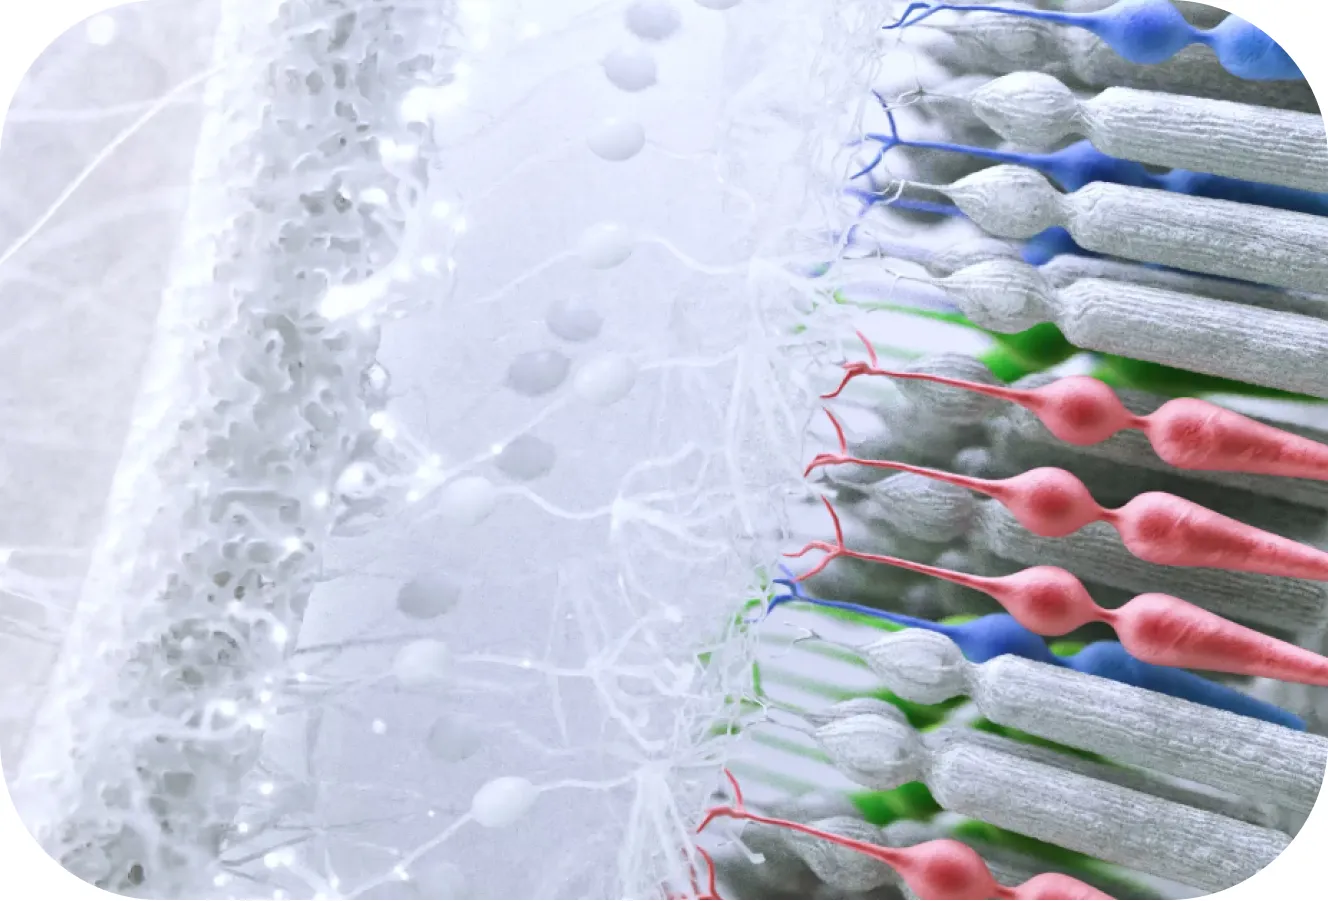

"text" => "Diffusion Optics Technology™ integrates thousands of light scattering elements called dots that mimic more natural contrast at all distances."

"sticky_title" => "Our lenses manage contrast by softly scattering light"

"sticky_list_0_text" => "Before it hits the retina"

"sticky_list_1_text" => "Before the retina detects artificial contrast and signals the eye to elongate"

"intro" => "Diffusion Optics Technology™ is a new and unique lens technology designs to mimic more natural contrast to help slow down axial elongation to control and reduce myopia progression¹ "

"contrast_sticky_text" => "Artificially high levels of contrast on the retina signal the eye to elongate. Our modern urban lifestyles come with artificial contrast (reading, using electronic screens...)."